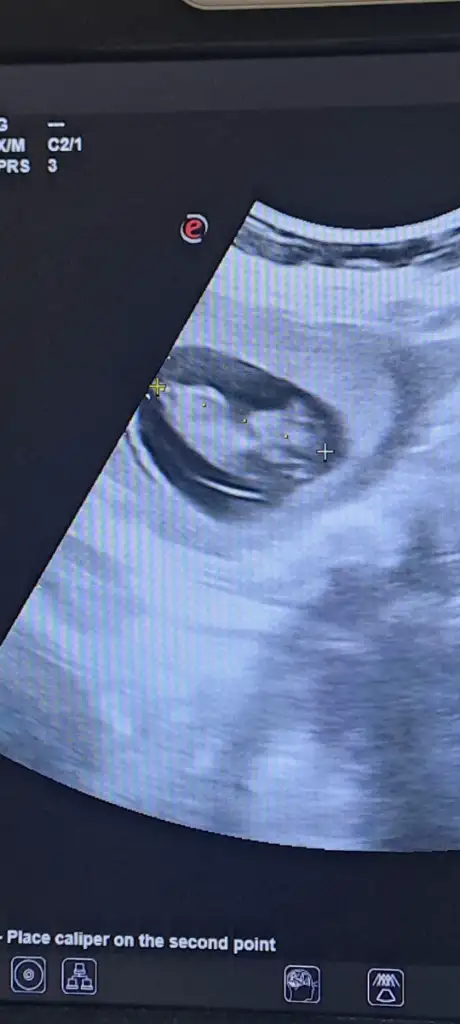

Banada bı yorum yapın bacılarım 12 haftalık görüntüsü